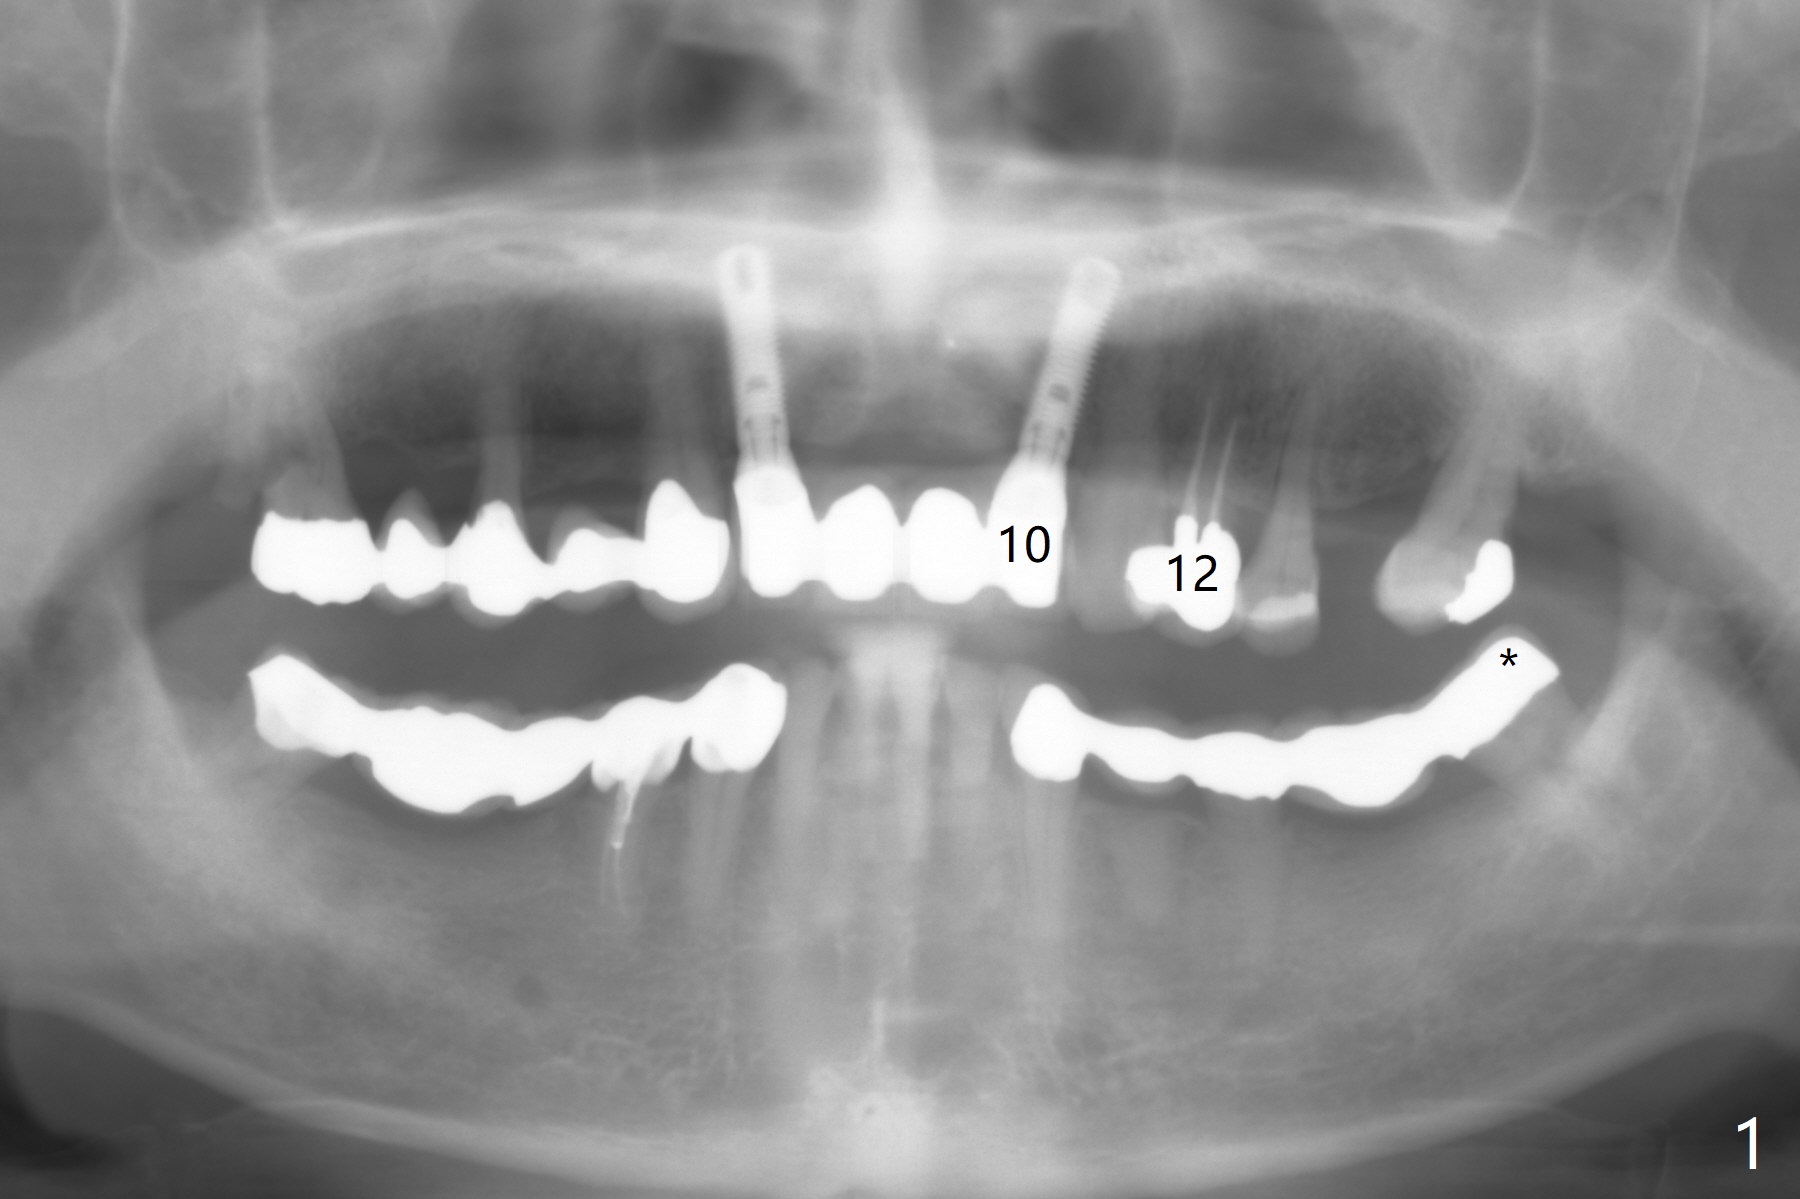

A 64-year-old man has multiple restorations. The tooth #2 seems to have root resorption. The tooth #27 has recently finished RCT. It appears necessary to establish sound occlusion on the left side by placing an implant at #14. First at all, the mesially tilted tooth #15 needs to be uprighted (Fig.2). The implant crown at #10 will be used as an anterior anchorage, since the three teeth (#11-13) are usually not strong enough to distalize the 2nd molar. To prevent debracketing at #10, a diamond bur will be used to roughen the crown surface and new bonding agent is applied. The second easily debracketing spot is #12 (crown), which could be used bicuspid band. The 3rd option to reduce debracketing is not to use rectangular wire initially. When the space at #14 increases to 8 mm mesiodistally, an implant will be placed. Once the implant is osteointegrated, a band is applied. From that point on, a rectangular wire could be used. If debracketing occurs at #10, it does not matter, as the posterior anchorage has taken over. Save all of wires used initially, since wires may have to return to thinner ones when #14 band is loaded. To unlock the occlusion (to distalize #15 without interference), composite will be applied to one of FPDs on the right side. The distal marginal ridge of the tooth #18 (Fig.1 *) may need to be trimmed.